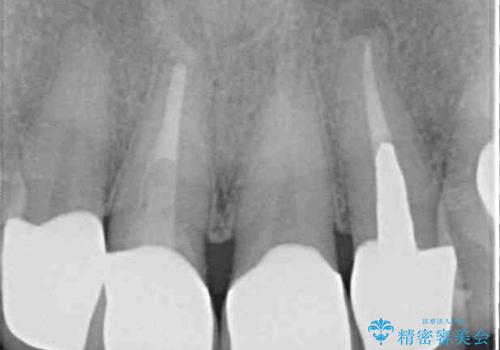

左右対称で明るく自然な前歯に仕上げることができました。